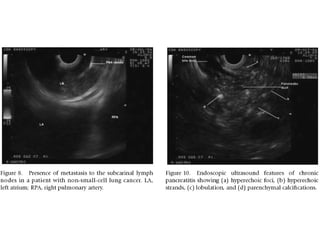

Lung Cancer

ATS Lymph Node Map

Surgery and then Recurrence?

EUS guided FNA of Area 7 LN